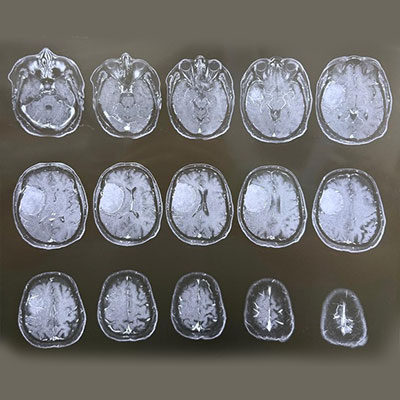

Surgical Highlights